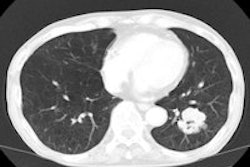

An innovative lung cancer screening pilot project in Northern Ireland designed to target selected patients older than 50 began at the end of November. The scheme is based on sensitive, low-cost chest x-ray, the first port of call to exclude lung cancer, according to consultant radiologist Dr. Stephen Hall from the Southern Health and Social Care Trust.

He pointed to the benefit of x-ray screening -- x-ray being sensitive enough to detect early lung cancer but obviating the extra cost streams associated with detection of subtle abnormalities by CT necessitating follow-up investigation.